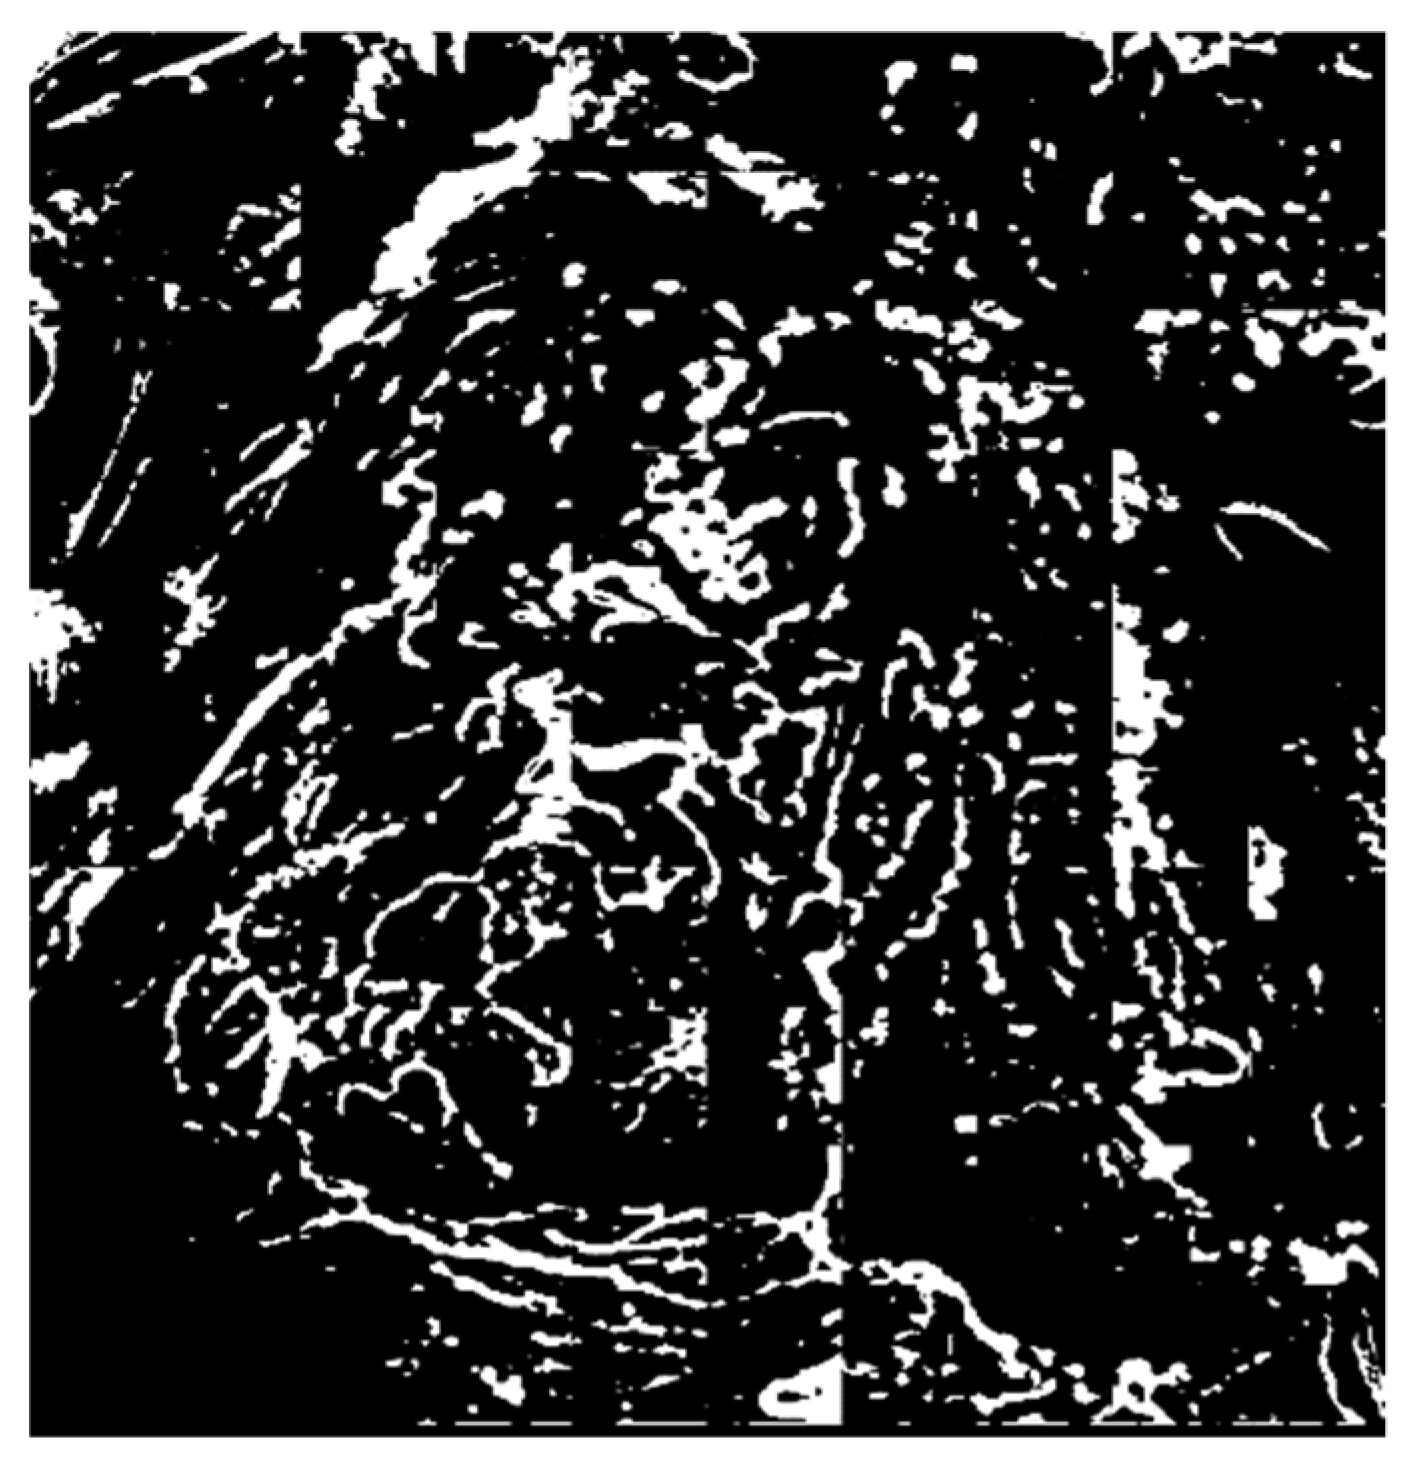

3.2.1. Extraction of the Microvessel Candidate Region Using Niblack’s Binarization

3.2.2. Noise Elimination in the Vascular Boundary Region Using a Fast Fourier High-Frequency Filter